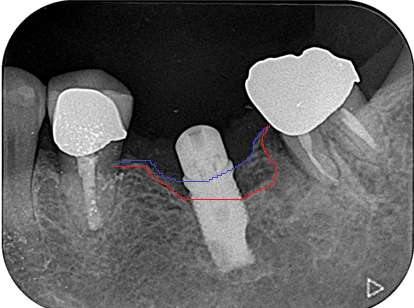

レントゲン写真では本来青線部分まで骨がないといけないのですが、赤線部分まで骨が溶けている状態です。

初診時は左下のインプラント(上部の被せ物は除去されていました)周りがとても腫れており、まずは膿を出すため切開排膿処置が必要な状態でした。かなり膿が溜まっていました。

初診時患者さんはまずは腫れを何とかしてほしいとのことでその後は今後このインプラントはまた使っていけるのか心配されていました。一時的にインプラント周りの腫れは引きましたがまたしばらくするとインプラント周りから膿が出てくるようになったため根本的な治療をしていかないといけないと診断しました。まずは徹底的なインプラント周りのお掃除(スケーリング・SRP)を行いました。それでも腫れの引きがいまいちだったため外科的治療で治していく方針に移行し、歯肉を切開ししっかりインプラント周りの状態を確認しました。インプラント周りの骨がレントゲン画像よりも溶けており、ボルトのギザギザ部分には黄色い汚れがかなり強くこびりついていました。それをしっかり除去してインプラントに汚れが再度つかないように徹底的に骨から露出しているインプラント体を研磨し滑沢にしました。